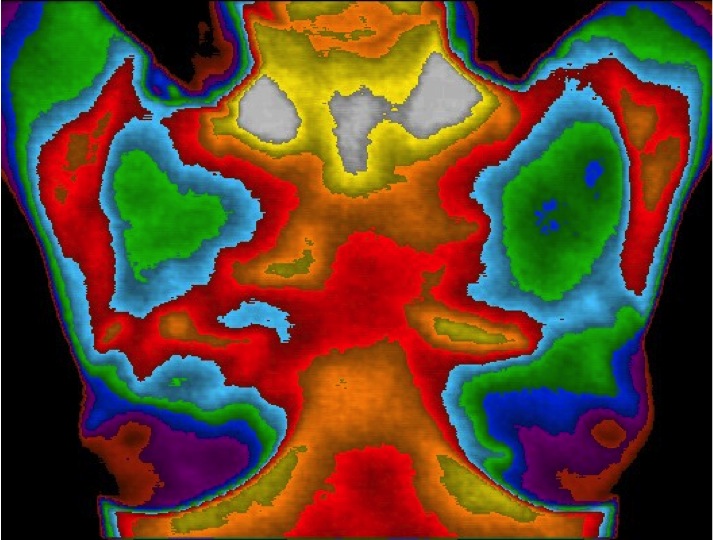

BEFORE Treatment  AFTER Treatment

The pre-treatment images display a specific vascular

pattern typical of estrogen dominance / progesterone

deficiency.

The post-treatment images show a marked improvement

after 6 months administration of transdermal

progesterone.

The implications in breast cancer prevention are significant!